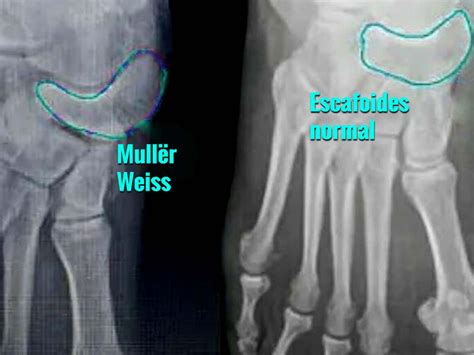

Mueller Weiss Syndrome is a rare degenerative disease of the navicular bone, a small, boat-shaped bone located in the midfoot. Unlike fractures caused by acute trauma, this syndrome occurs when the bone loses its blood supply, leading to fragmentation and collapse. While the exact cause remains somewhat elusive, it is frequently associated with mechanical stress, congenital anomalies, or systemic conditions that impede vascular flow.

Diagnosing Mueller Weiss Syndrome requires a comprehensive evaluation by a foot and ankle specialist. Because the symptoms can mimic other conditions like tarsal coalition or arthritis, imaging is essential for a precise diagnosis.

X-ray (Weight-bearing) The primary tool to visualize the navicular bone's fragmentation and collapse.